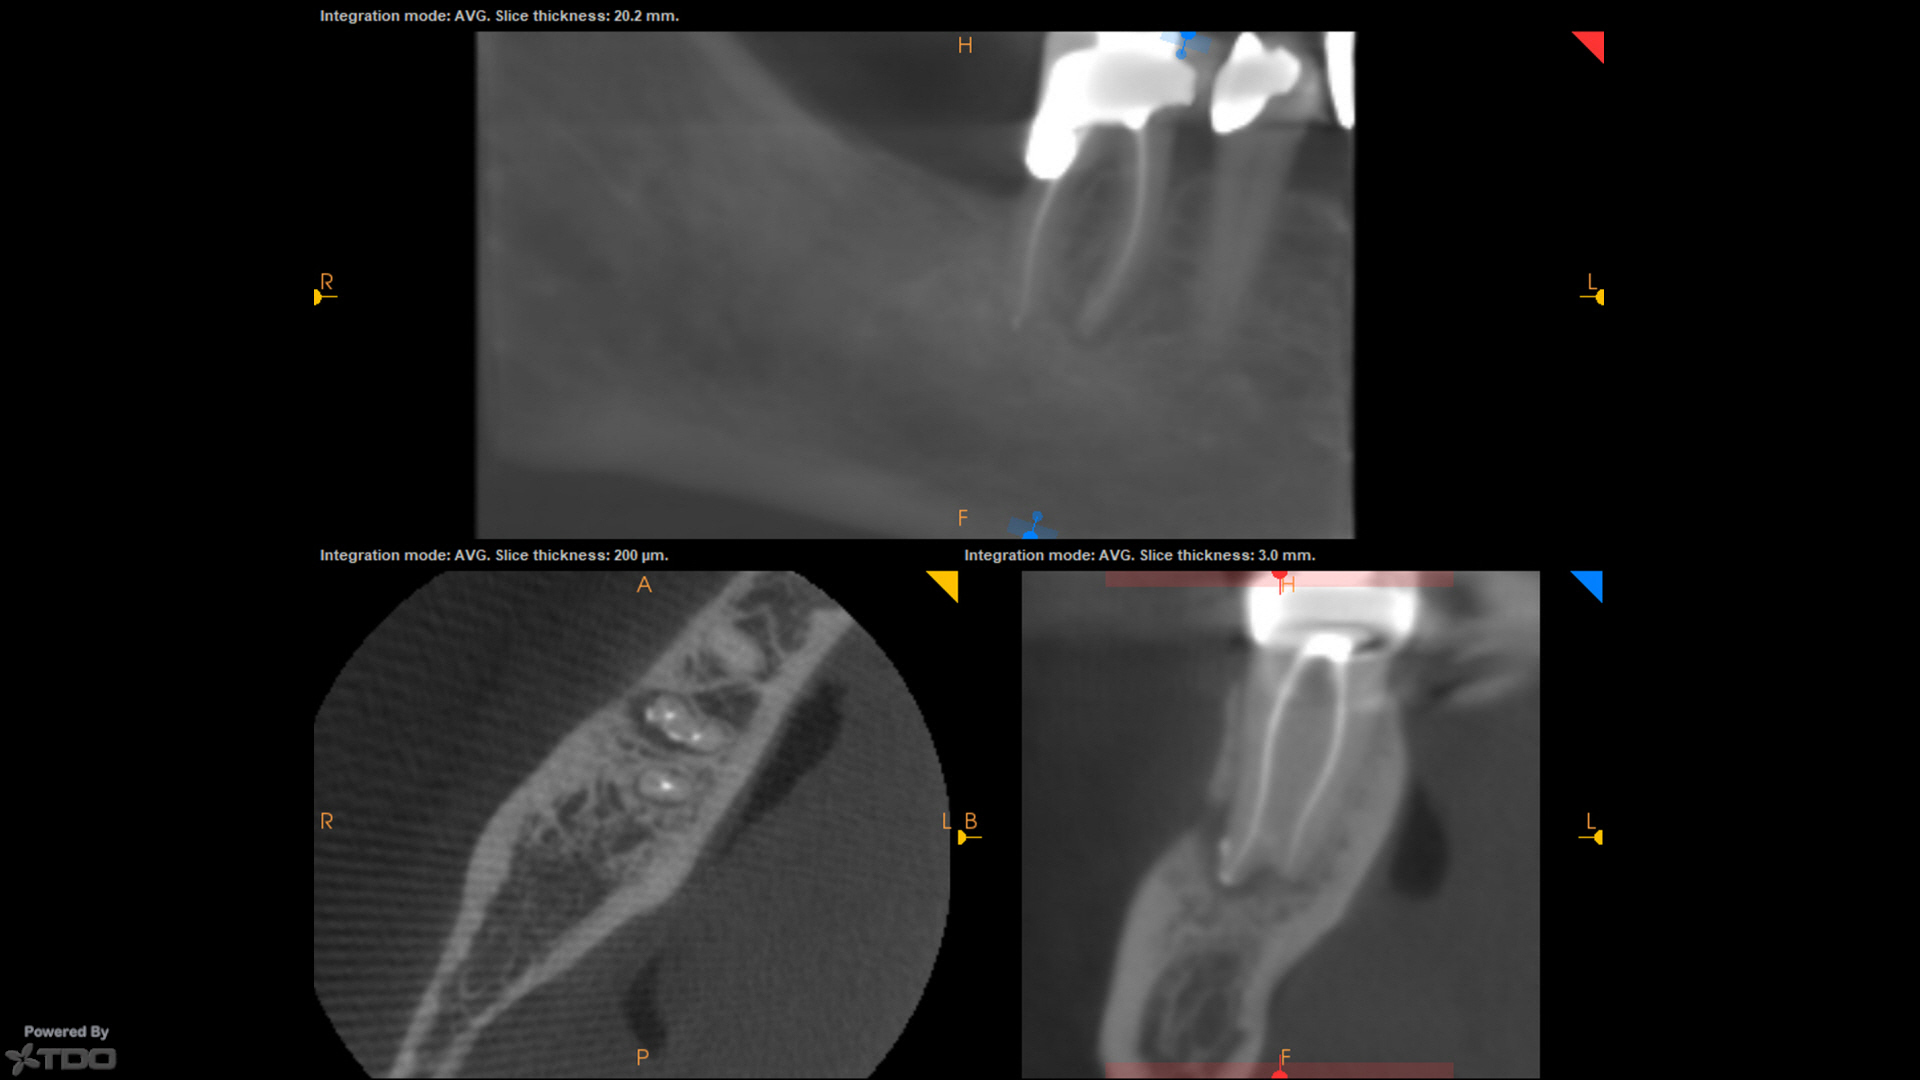

Here are a couple of single-cone BC sealer cases from today, and last week.

Both are SSW 17/V.04, single-cone (#20 cone…very thin and flimsy).

No downpack, no backfill.

CBCT post-op on the one from today demonstrating some apical anatomy if that tickles your fancy.